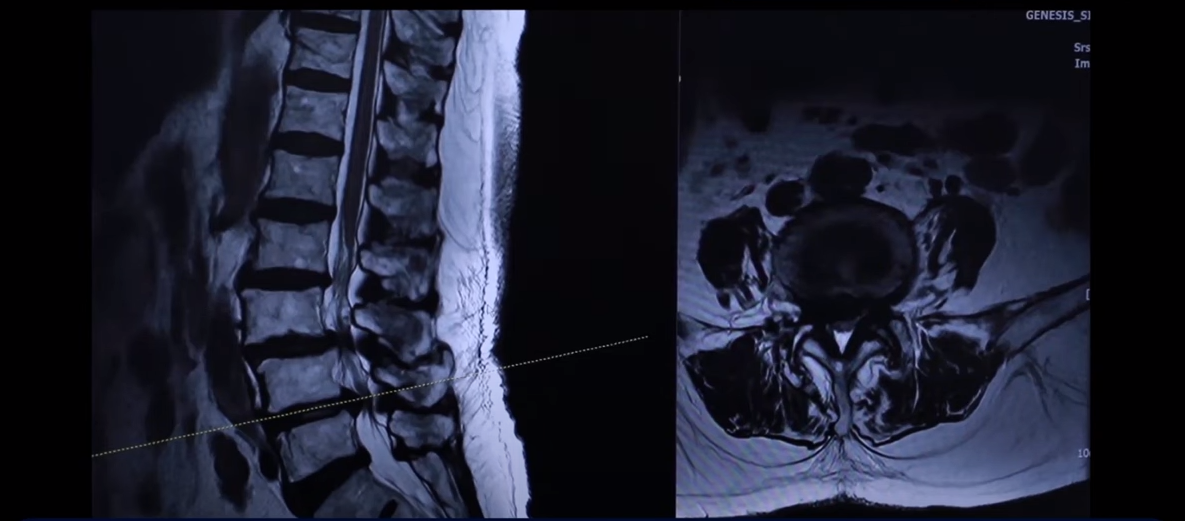

이분 76세 여자 환자분 MRI를 보겠습니다. 이분 MRI를 보시면 보시다시피 허리 여러 마디가 퇴행돼 있고 전방전위가 있습니다. 뼈가 밀려나가 있죠.

그리고 이렇게 뼈가 밀려나간 전방전위증을 가지신 분들은 허리가 오랫동안 아프신 분들이 많습니다. 이분도 한 5년 정도 허리가 아프셨고 그때그때 신경 주사 맞으면서 버티고 사셨는데 신경주사라는 건 맞다 보면 점점 효과가 떨어집니다. 그리고 결국은 다리 증상들이 심하게 생겨서 걷지를 못하게 되시는 거죠. 걷는 거리도 점점 짧아지고 다리는 왜 저리게 되냐면 이분의 이렇게 전방전위증이 있는 마디를 보면 척추관이 좀 좁아져 있지만 아주 많이 좁지 않습니다.

어떻게 척추관 협착증이 수술 없이 치료가 될 수 있는지 많은 분들이 이렇게 신경이 눌려 있으면 어떻게든 이 주변을 수술로 파내서 신경 구멍을 넓혀줘야만 한다고 생각을 하는데, 전방전위증, 척추관 협착증이 증상이 생기고 악화되는 이유는 신경 구멍만이 좁아져서 그런 게 아니라 아니라 동시에 이분이 나이가 들면서 76세시죠. 그러면 근육이 동시에 나빠지는 겁니다. 어떻게 나빠지냐 이미 40대부터 근육이 빠른 속도로 줄기 시작해서 76세면 젊었을 때 근육의 50%~60%밖에 남지 않습니다.

그런 근육을 가지고 계속 활동을 하고 걷고 앉아 있고 허리를 구부렸다 폈다 하고 힘을 쓰다 보니까 그 근육들이 뭉치고 굳어버리고 뒤틀리고 아프게 되는 것이죠. 그래서 근육이 기능이 떨어지면서 허리를 지탱하지 못하면 바로 이런 곳에서 신경 눌림 증상이 생기는 겁니다.

그래서 이렇게 근육 상태가 어떤지 이렇게 객관적으로 볼 수 있는 부분도 MRI에서 보실 수 있습니다. 그만큼 근육이 안 좋아지니까 나이가 드시면서 또 이런 근육들이 뭉쳐 있고 굳어 있고 또 기능을 잘 못하게 되니까 또 근육 자체도 뭉쳐 있으면 아픕니다. 그러니까 허리를 잘 지탱하지 못하니까 이런 신경 구멍이 좁아진 곳에서 신경이 눌리는 겁니다. 허리를 잘 지탱할 수 있도록 근육 기능들을 살려주니까 훨씬 더 신경 눌림이 덜해지고 힘을 잘 쓸 수 있고 더 잘 걷게 되는 겁니다.